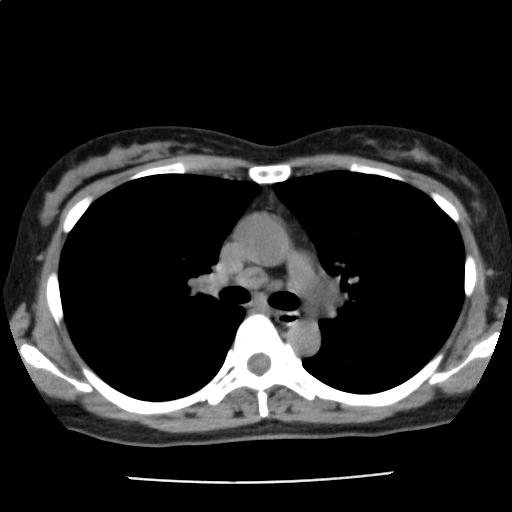

両肺に径数 mm~約9 mm の結節が多発しており(添付画像以外にも認める)、辺縁不整を認める。

多発肺転移の可能性をまず除外する必要があり、原発としては乳癌、膵癌などと考える。

縦隔リンパ節を散見する。胸水は認めない。

多発肺結節・縦隔リンパ節腫大:r/o 多発肺転移